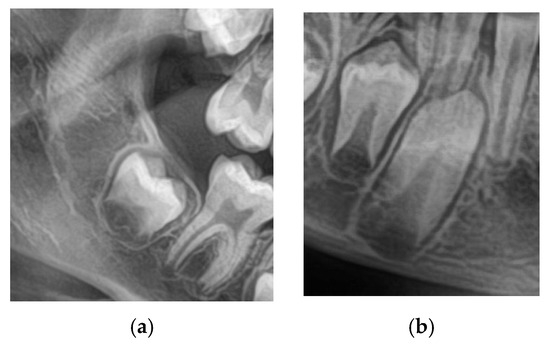

A total of 1200 digital OPGs were collected retrospectively from academic and private dental centers. The sample was 600 males and 600 females aged 8–16. The inclusion criteria were OPGs with adequate quality; both the lower 2nd molars and canines are clearly visualized as in Figure 1, no systemic disease, craniofacial syndrome, and no previous orthodontic treatment. Examinations with inadequate image quality, overlapping dental structures, or incomplete records were excluded.

Figure 1.

Both the lower 2nd molars and canines are clearly visualized as in OPG image.